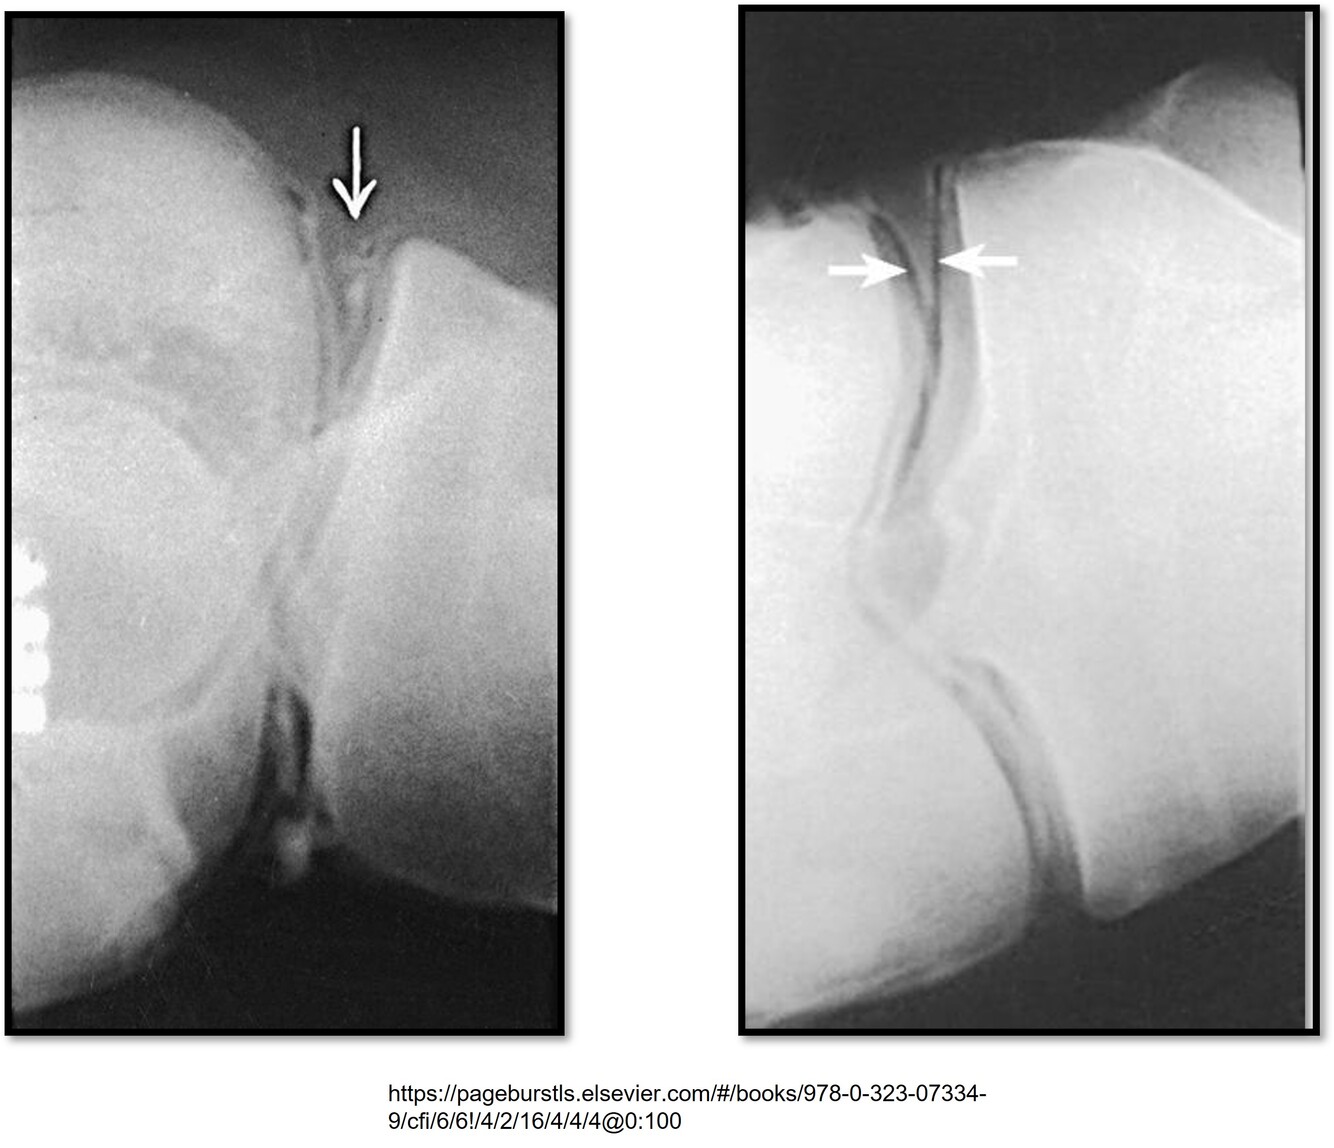

What pathology is this showing?

A torn vs. healthy meniscus

–Tears or degeneration of menisci

Where is double Contrast injected for a meniscal injury?

Into the lateral aspect of the suprapatellar recess

What views are done for meniscal imaging of the knee with arthrography?

-Images taken from prone to lateral to supine, rotating the knee 30 degrees each exposure

-Cross-table imaging required